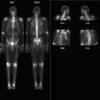

Nl Nuc Med

Date: 03/23/2004

Views: 4298